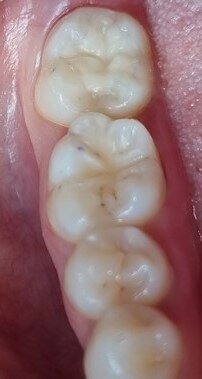

A 16-year-old female patient in good general health had received restorations in the mandibular molars owing to carious lesions in the recent past, and in light of her background, the patient requested a dental check-up at least once a year and had tried to develop good hygiene habits. When she came for a dental check-up, she mentioned new black pigmentation in the mandibular molars and sensitivity in the last molar of the fourth quadrant (Fig. 1). During the clinical examination, retentive areas were found in teeth #46 and 47. The composite restorations in the molars of the third quadrant were apparently in good condition.

Fig. 1: Non-cavitated carious lesions in teeth #46 and 47. The greyish aspect of the enamel and the hypersensitivity of tooth #47 experienced by the patient suggested an underlying dentine lesion requiring restorative treatment.